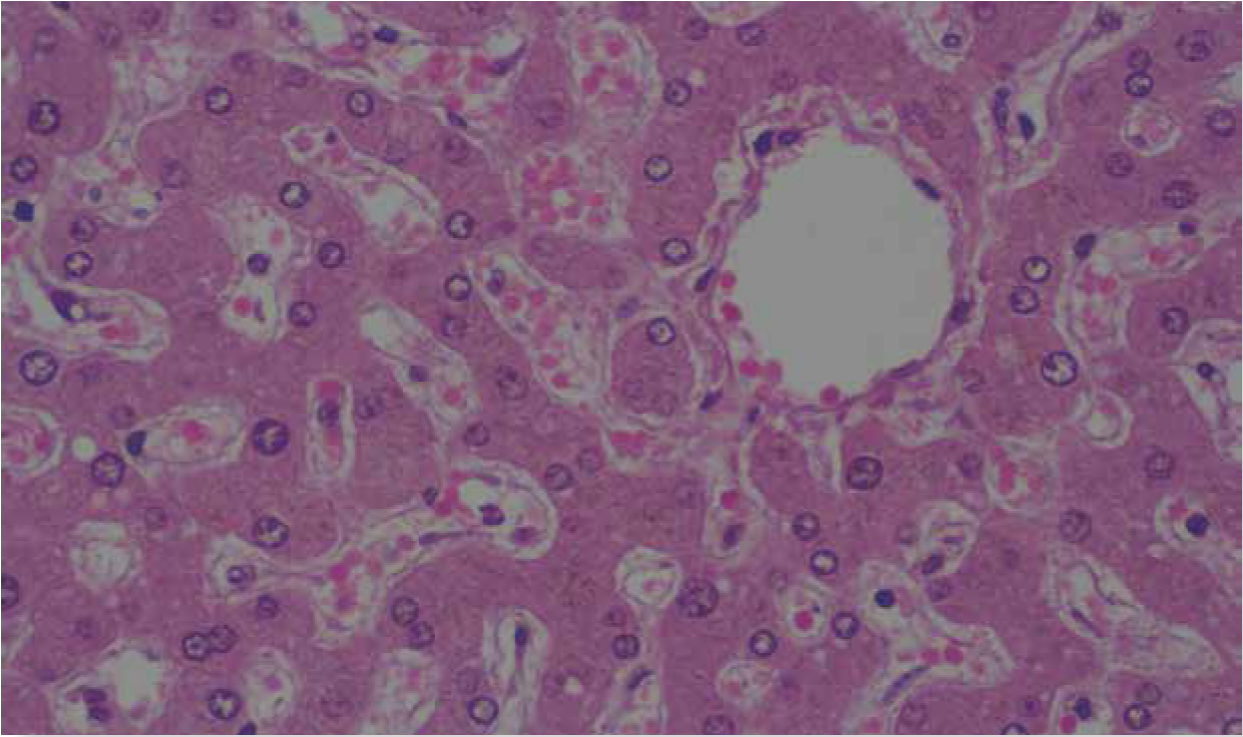

Para formar el parénquima hepático, las células se ordenan de la siguiente manera: los hepatocitos forman placas o muros que están flanqueados por sinusoides que drenan en las venas centrales. El espacio que queda entre la pared de los hepatocitos y la pared del sinusoide se llama espacio perisinusoidal (de Dissé), y las células de Kupffer y las de Ito se alojan en ese espacio (Figuras 1 y 2).

Figura 1 Corte histológico de hígado teñido con hematoxilinaeosina. Los espacios pálidos entre las placas de hepatocitos corresponde a los capilares sinusoidales.

Figura 2 En esta imagen observamos a las placas de hepatocitos flanqueadas por los sinusoides. El espacio entre la pared de los sinusoides y los hepatocitos es el espacio perisinusoidal. También se aprecia la vena central del lobulillo. Tinción HE.